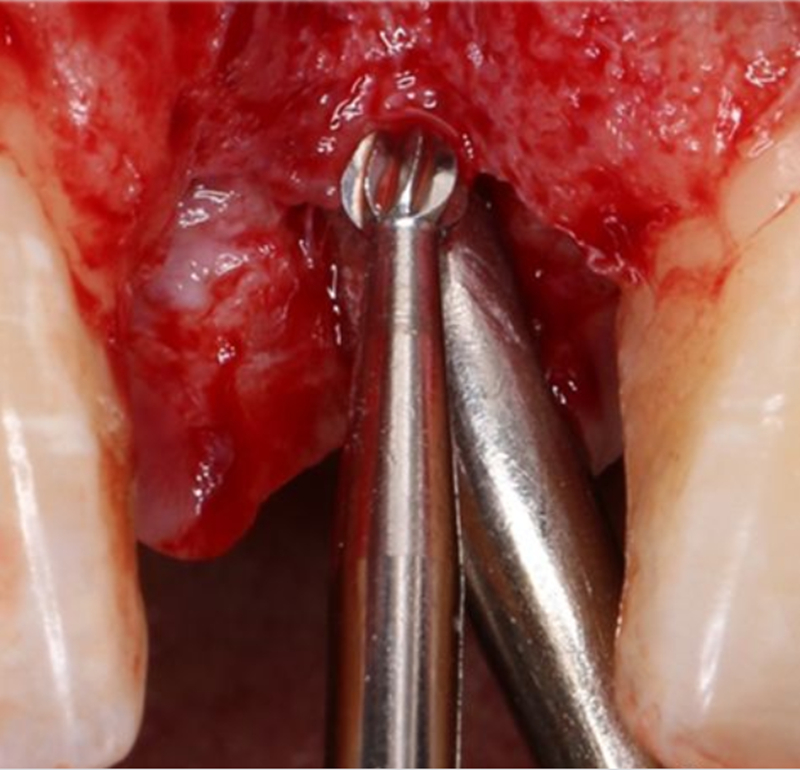

1.4mm小球鉆定點 △

2.3mm中號球鉆打開皮質(zhì)骨△

在易植美實時導(dǎo)航系統(tǒng)中,計算機引導(dǎo)球鉆精準按照術(shù)前設(shè)計定位△